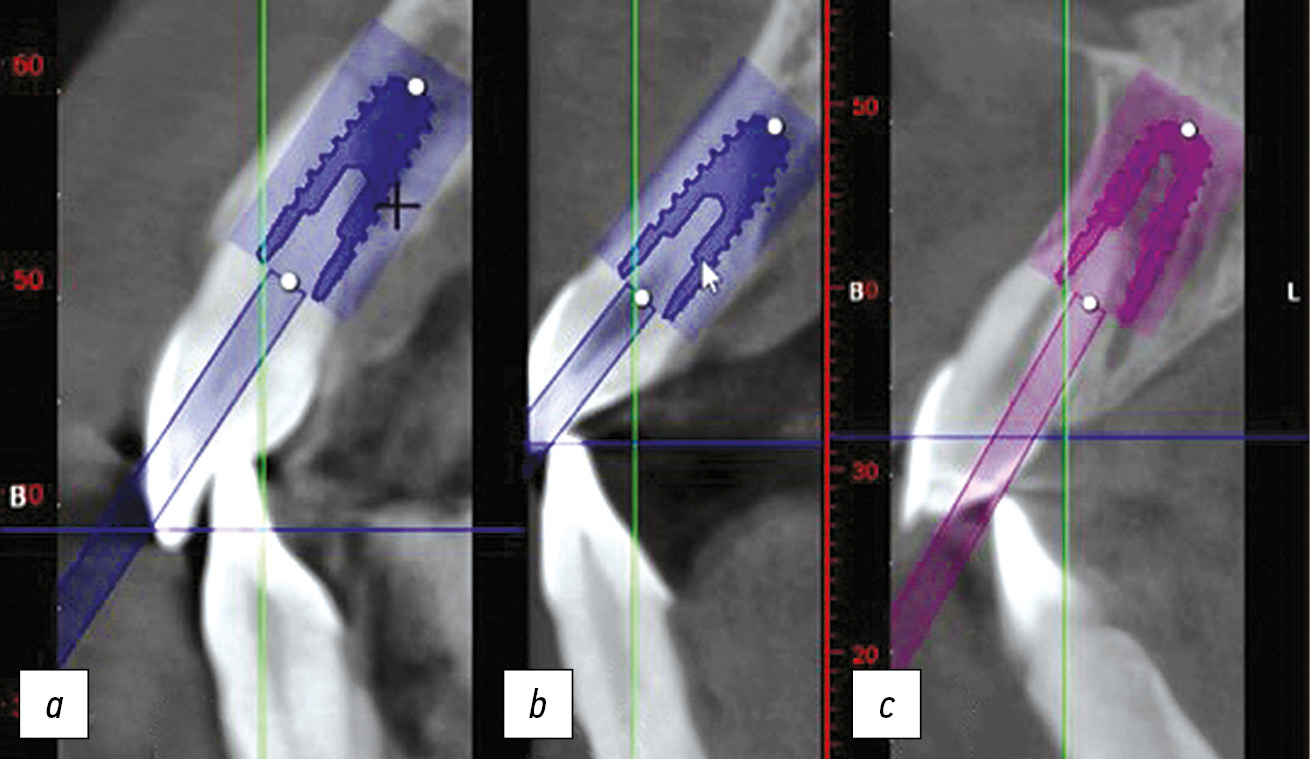

У данных пациентов проводился анализ КЛКТ-изображений на аппарате ProMax 3D Classic (Planmeca, Финляндия). В программе планирования имплантации ProMax 3D Classic оценивалась возможность удаления зуба 1.1 и установки имплантата с соблюдением протокола немедленной имплантации с возможностью изготовления коронки с винтовой фиксацией и выходом шахты винта у искусственной коронки на нёбную поверхность в каждой исследуемой группе. Выход шахты винта планировался на нёбной поверхности с отступом на 2–3 мм от режущего края коронки зуба для моделирования таким образом возможности изготовления цельноциркониевой коронки (рис. 3).

Рис. 3. Выход шахты винта: а) на вестибулярную поверхность; b) на режущий край; с) на нёбную поверхность.